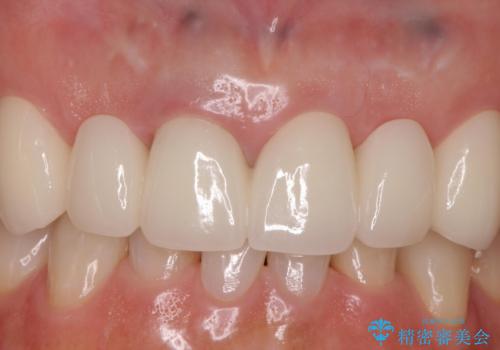

入れ歯を変えたい ブリッジでの修復治療

着脱の煩雑さがなくなり大変喜んでいただけました。

本数の多いブリッジは人工歯同士で色調を合わせることができるため審美性に優れています。